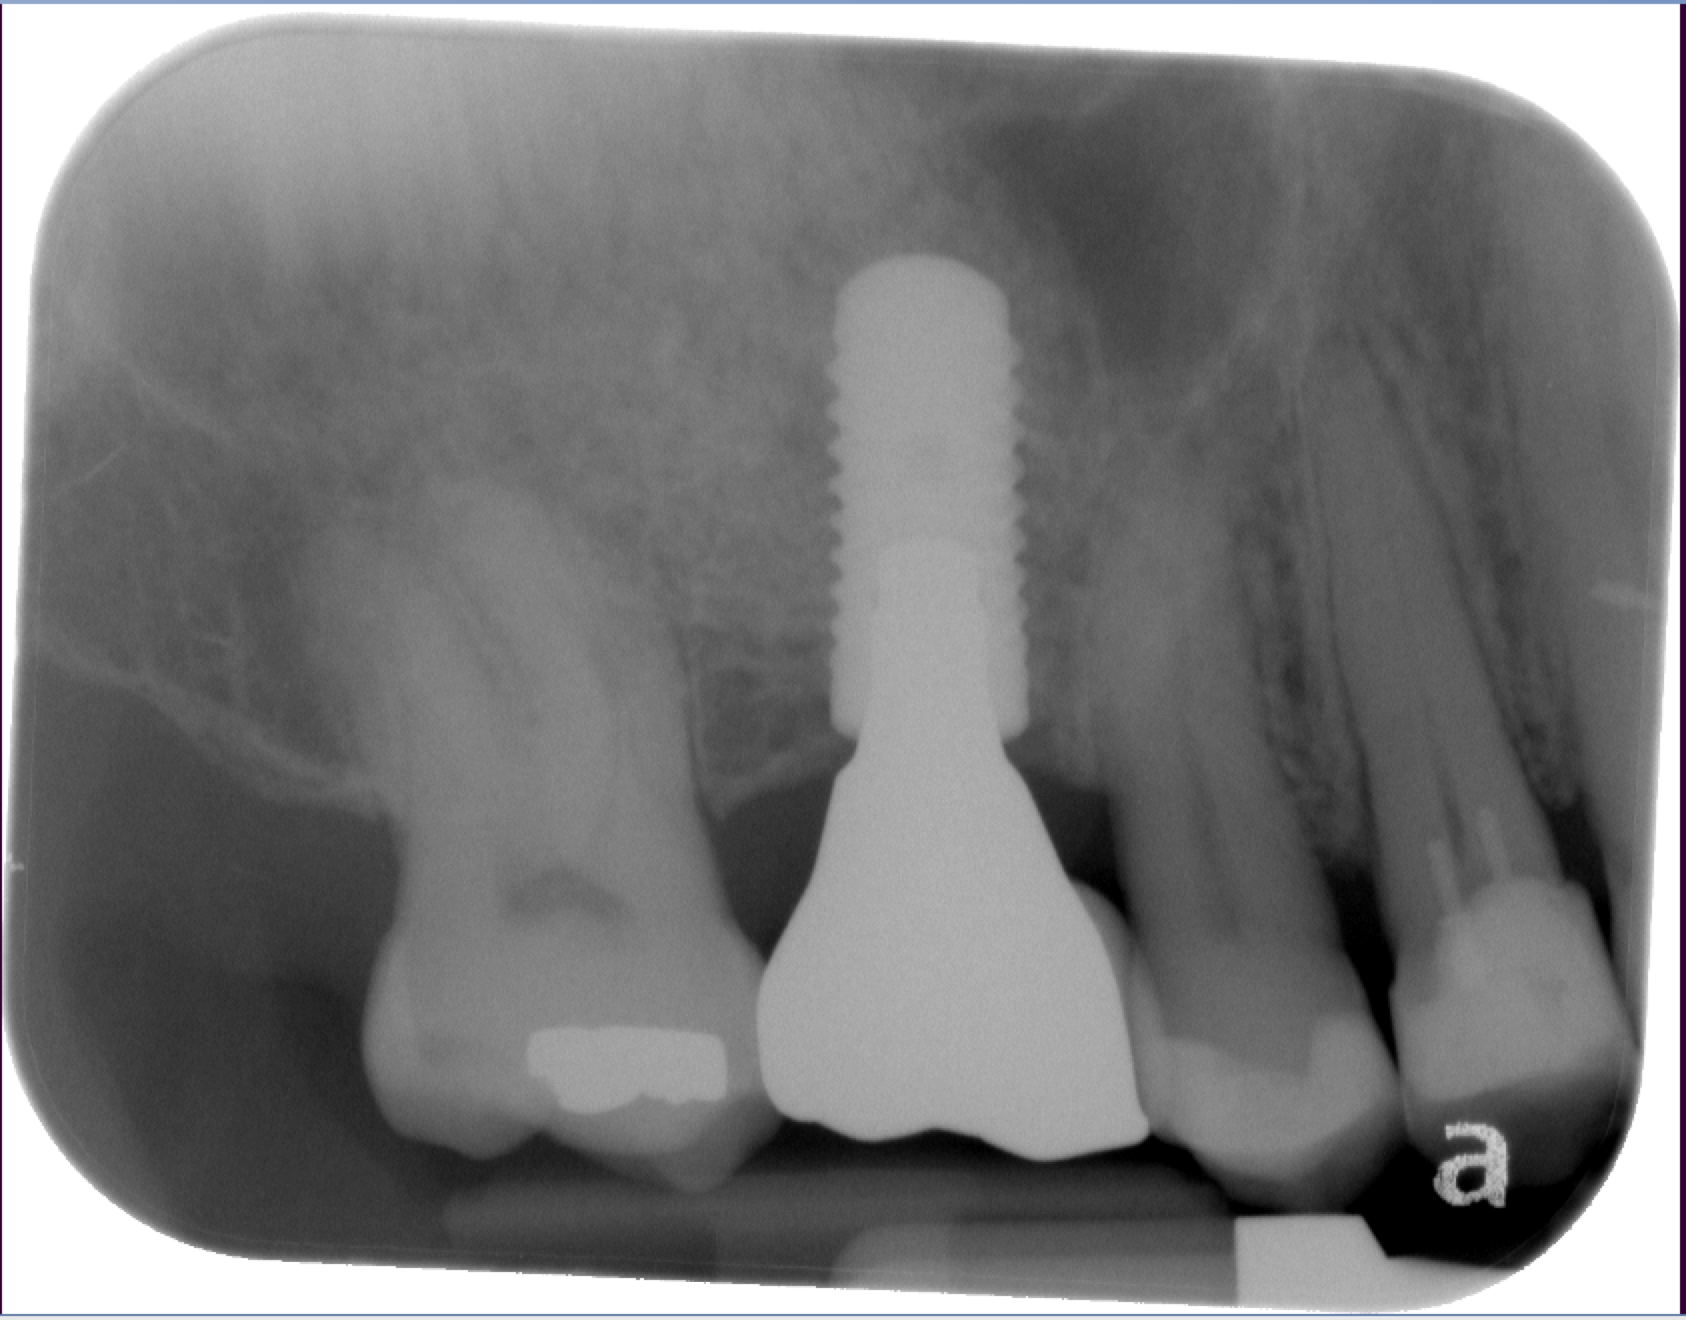

Sinus Lift Implant Vancouver Burnaby Periodontist Implant Dentist IMPreESS Perio

Dental Implant Centre in Vancouver Burnaby Sinus Lift Dental implant Surgery Dr. Noroozi Implant Specialist IMPrESS Perio Implant Center.001

Sinus Lift, Bone Graft, Implants Dr. Noroozi IMPrESS Perio Implant Center